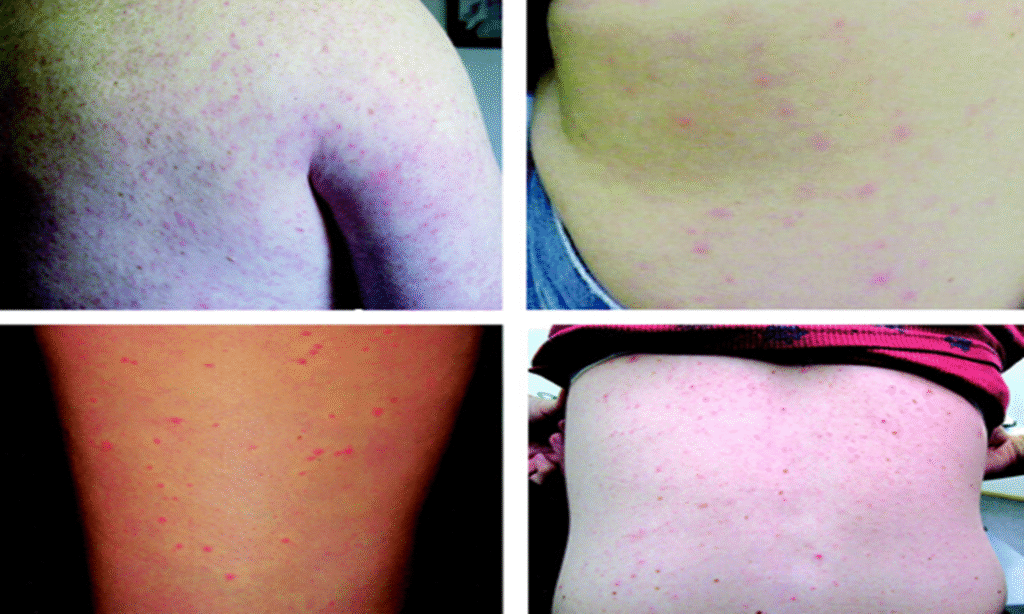

• მაკულოპაპულური გამონაყარი დასავლეთ ნილოსის ვირუსული დაავადების დროს (სურათი 2).

(სურათი 2)

ოთხ პაციენტს აღენიშნება დასავლეთ ნილოსის ვირუსის ცხელება და ერითემატოზული, მაკულოპაპულური გამონაყარი ზურგზე (ზედა მარცხენა მხარე), გვერდზე (ზედა მარჯვენა მხარე), ბარძაყის უკანა მხარეს (ქვედა მარცხენა მხარე) და ზურგზე (ქვედა მარჯვენა მხარე)